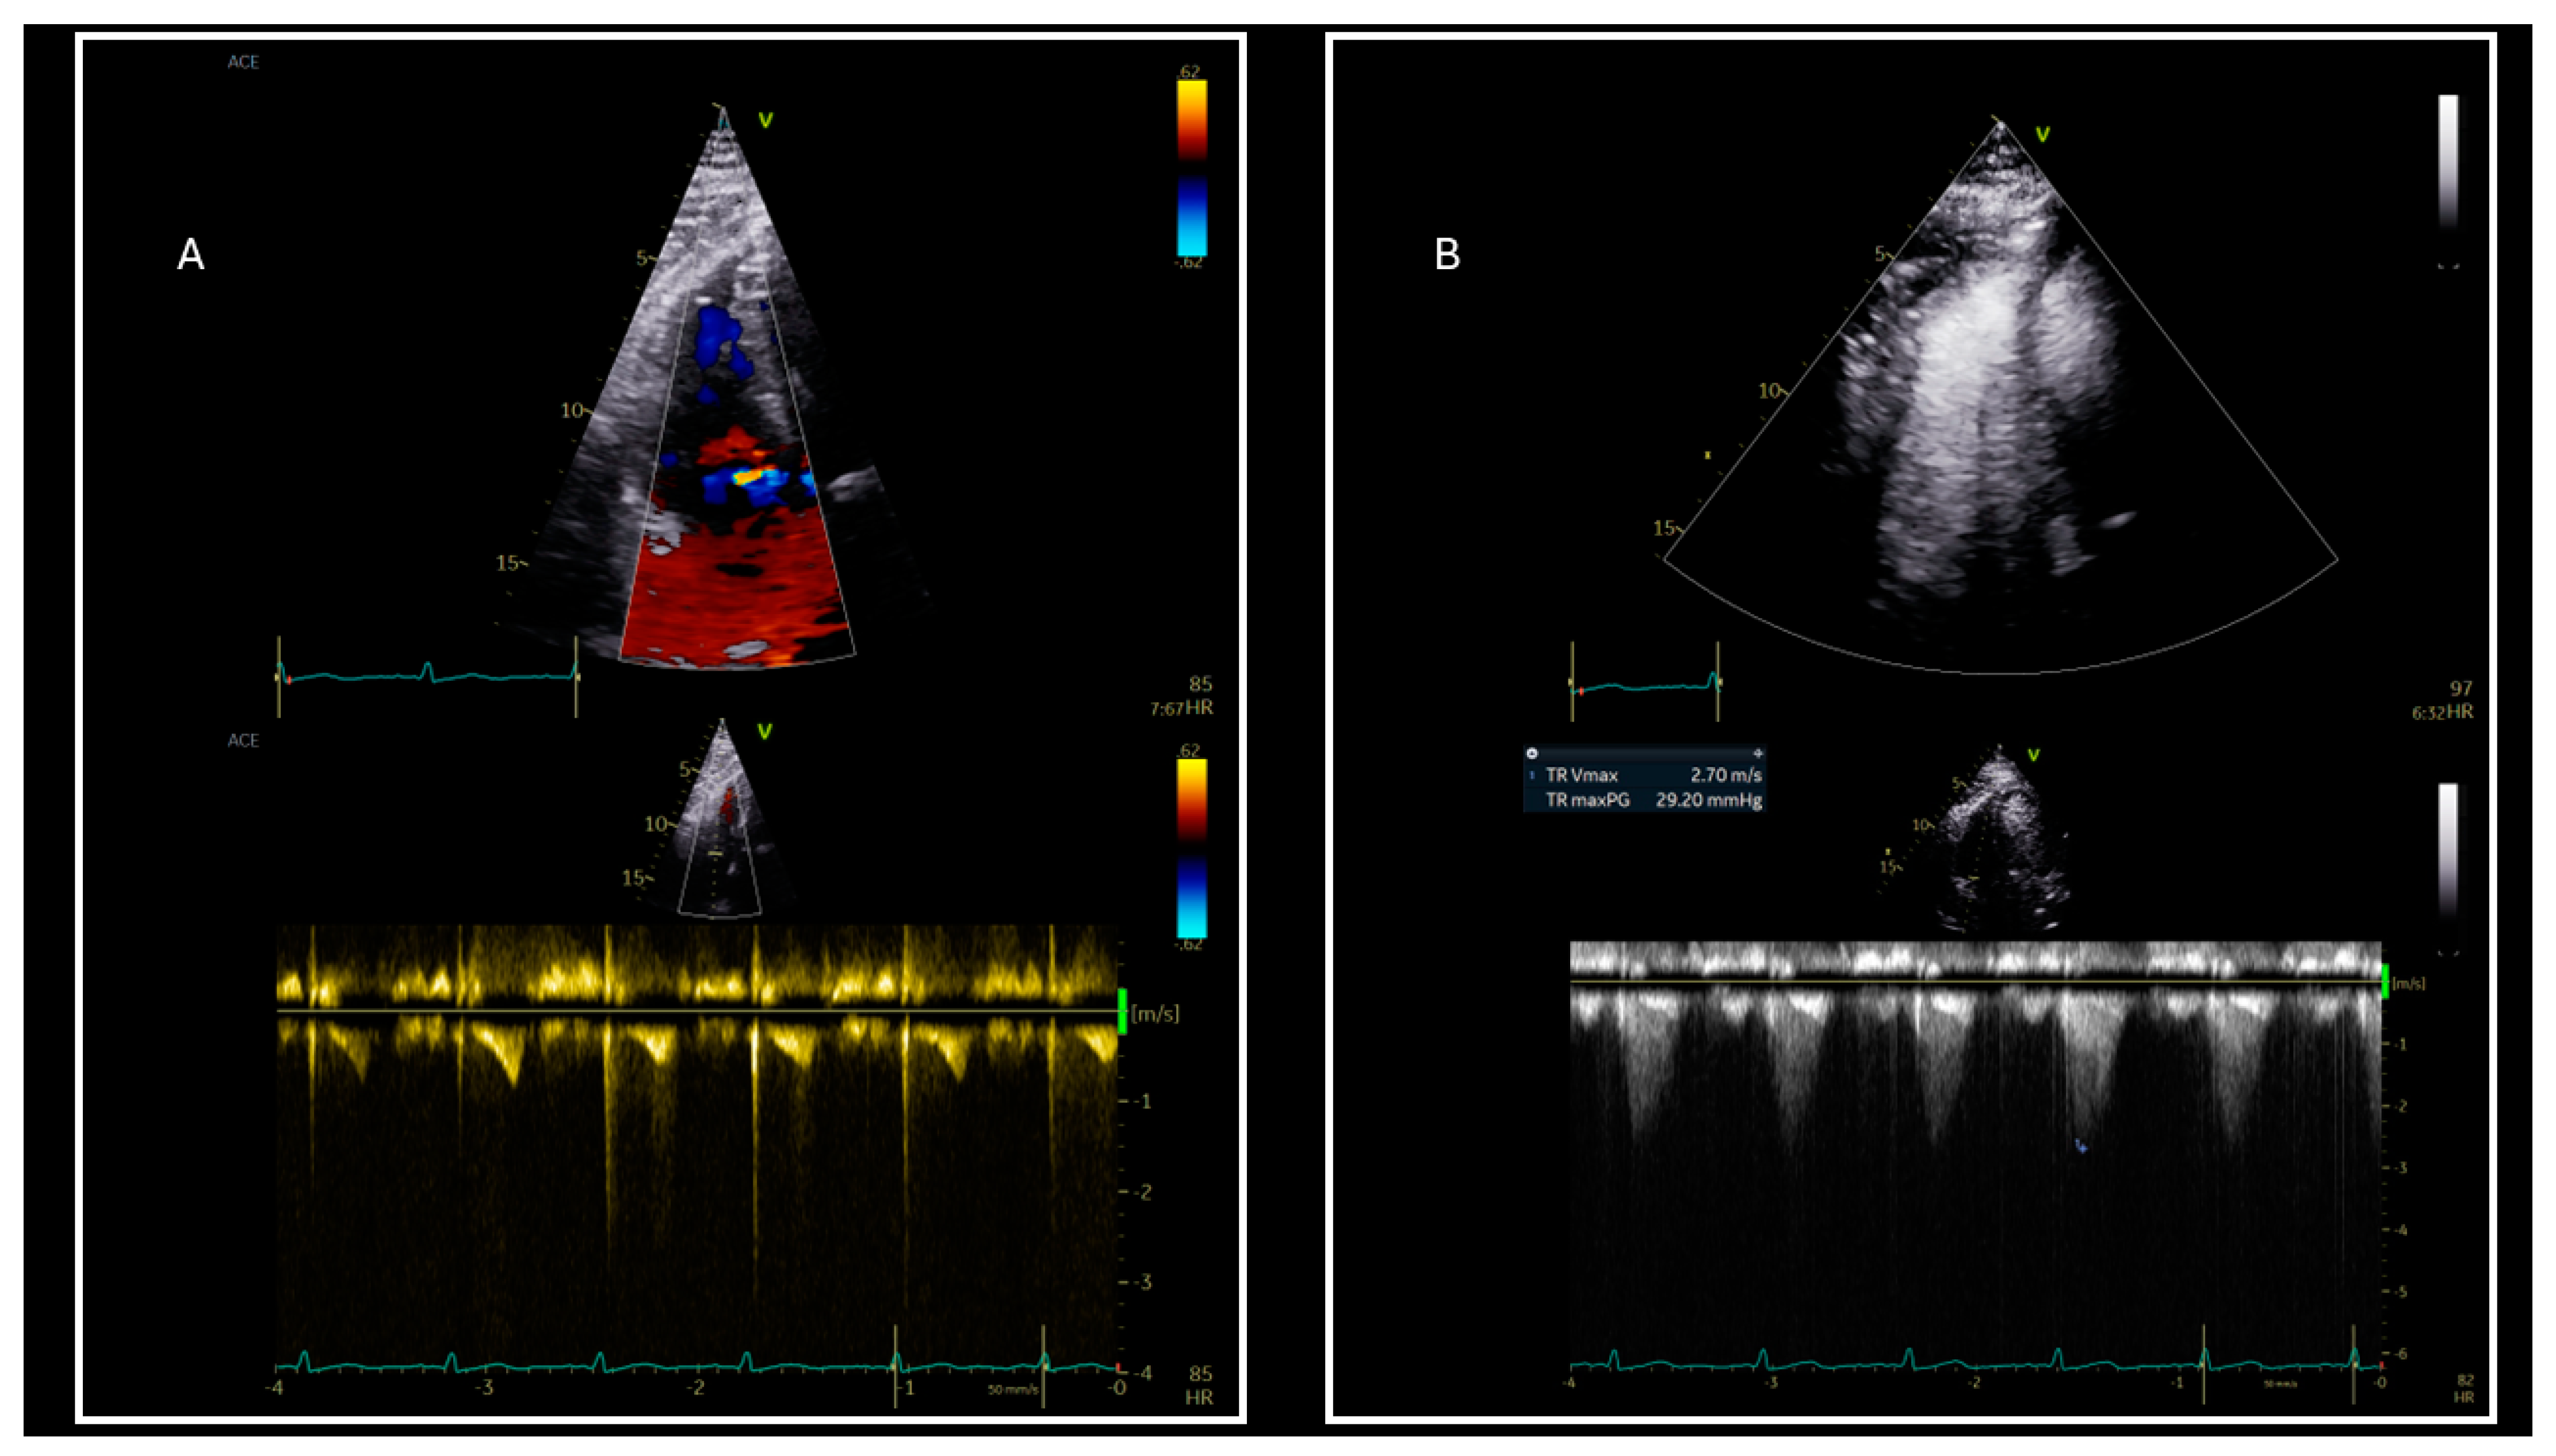

5. Diastolic Dysfunction Assessment in Individuals Who Are Obese in Atrial Fibrillation

6. Pulmonary Hypertension and Diastolic Dysfunction in Obese